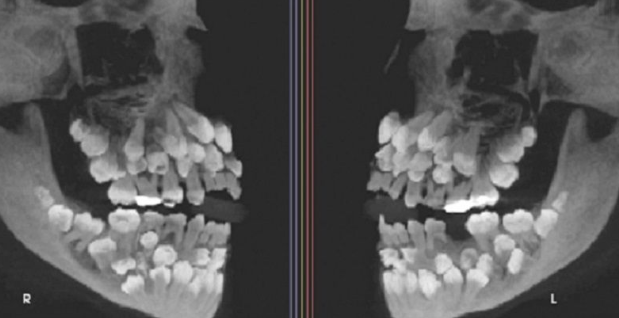

한 소녀의 입 안에 무려 81개에 달하는 치아가 발견돼 학계에 큰 충격을 주고 있다.

엑스레이 촬영 결과 소녀의 입 안에 유치 18개, 영구치 32개, 과잉치 31개 등 총 81개의 치아가 발견된 것.

브라질 미나스제라이스주 주이스지포라 연방대학교 치과병원 연구팀은 소녀에게 '다발성 과잉치증(multiple hyperdontia)'을 진단했다. 덧붙여 "보통 1~2개의 과잉치만 발견되는데 30개가 넘는 과잉치가 확인된 것은 전 세계적으로 매우 드물다"며 놀라워했다.